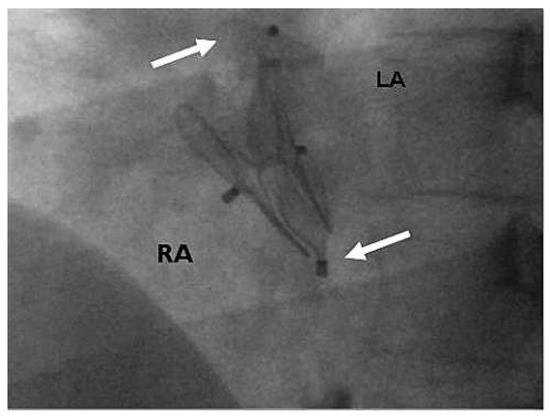

Triple Percutaneous Patent Foramen Ovale Closure

by Fabien Praz, Andreas Wahl and Bernhard Meier

Cardiovasc. Med. 2012, 15(9), 253; https://doi.org/10.4414/cvm.2012.01692 - 26 Sep 2012

Percutaneous patent foramen ovale (PFO) closure is mainly performed for secondary prevention of presumed paradoxical embolism. Since a residual shunt has been associated with recurrent events, complete PFO closure is desirable. We report the first case of ultimately successful percutaneous PFO closure using [...] Read more.

Percutaneous patent foramen ovale (PFO) closure is mainly performed for secondary prevention of presumed paradoxical embolism. Since a residual shunt has been associated with recurrent events, complete PFO closure is desirable. We report the first case of ultimately successful percutaneous PFO closure using successively 3 Amplatzer PFO devices. Full article

Show Figures

Figure 1